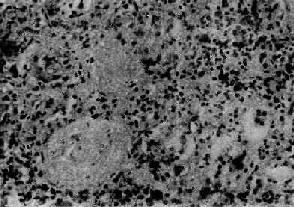

電鏡下腎小球基底膜厚薄不均,上皮細胞足突融合。系膜基質增多,伴電子緻密物沉積。

2.電鏡檢查有大量蛋白尿的病例大部分或全部腎小球顯示瀰漫性或節段性足突改變。早期在毛細血管壁和(或)系膜區可見泡沫細胞、系膜基質增加及部分毛細血管塌陷。內皮細胞下及系膜區有電子緻密物沉積,系膜細胞增生,大塊的電子緻密物與光鏡下的玻璃樣變及免疫螢光IgM和C3沉積相對應。球旁系膜區及內皮細胞下亦可見細顆粒狀電子緻密物沉積。